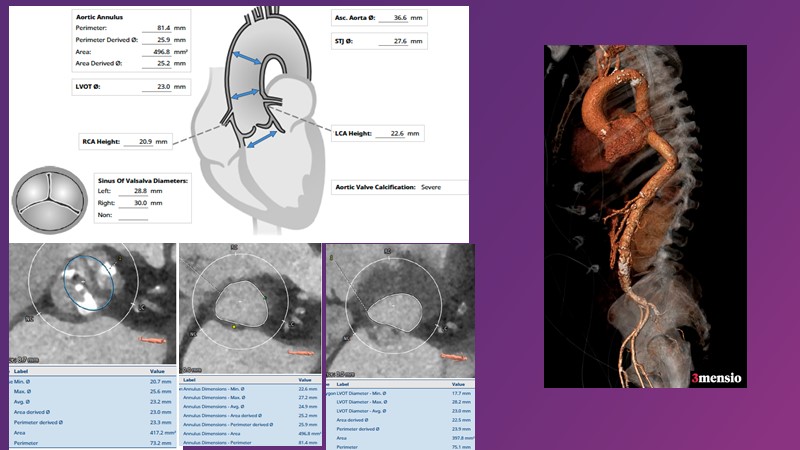

This session reflects on the importance of device choice and implantation technique in complex TAVI procedures. Learn how to anticipate the risks of a valve-in-valve procedure in small surgical prostheses, and discover the latest technological evolutions for treating patients with complex anatomy.

- To appreciate the importance of device choice and implantation technique in complex TAVI procedures

- To learn how to anticipate the risks of a valve-in-valve procedure in small surgical prostheses

- To discern the latest technological evolutions for treating patients with complex anatomy